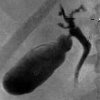

Холецистография

Холецистография – методика рентгеноконтрастного исследования состояния желчного пузыря. Холецистография выполняется для определения положения, величины, формы, контуров, структуры и функционального состояния желчного пузыря. Всего в Твери найдено 4 клиники, где можно сделать холецистографию.